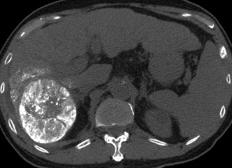

Adaptándosealosrequerimientosmédicosquedíaadíaseconvierten enunretoparadarconelresultadoexactodepatologíasdelospacientes,llegaaClínicaCórdobaunequipodetomografíarevolucionario,el másavanzadodelestadoactualmente:elToshibaAquilionCXL128.

Elcuadrodesaluddeunpaciente requierederespuestasinmediatasa travésdeunestudioexactoenelme‐nortiempoposible.Esteequipoescatalogado comounaherramientadeúltimatecnología espectralquecuentaconeldoblededetecto‐resomás,enrelacióncontomógrafos convencionalesqueencontramosenrestodel estado.Cuentaconuntubode128detectores loquesetraduceenvelocidad,nitidezymayor precisióneneldiagnóstico.

Permiteevaluarnosololosdiversosórganos delcuerpocomoeltejidocerebral,sino tambiénlosvasossanguíneos.Seutilizaen estudiosderutinaparaanalizarelcuello,cere‐bro,tóraxylosdiferentesórganosdelabdo‐men,asícomoloshuesos.Susoftwarepermi‐teprocesarreconstrucciones3Dcongráficos derealidadvirtualdeexcelentecalidad,que sondegranutilidadparaclínicosycirujanos. Conestatecnologíasereduceladosisde radiaciónenhastaun80%,estolohaceuna excelenteopciónenpacientespediátricosy adicionalmentesoportahasta205kgdepeso, muyútilenpacientesbariátricos.

Estáequipadoconunagrancantidadde aplicacionessofisticadasqueabarcan especialmenteestudioscardiovasculares:Se puedeevaluarelcorazón,analizarmediante angiotomografíacoronariasusarteriasyrea‐lizarprotocolosparapacientesaquienesse lesplanearealizarunreemplazovalvular.Tie‐neunaresoluciónespacialquebrindamejor definicióndeimagenenestudioscomo angiotomografíademiembrospélvicos, angiotomografíaaórtica,angiotomografía cerebral,angiotomografíadetroncossupra‐aórticos,loquepermitediagnosticaryplanifi‐carlosprocedimientosencasoscomoaneu‐rismas,estenosisoanomalíasvasculares. Cuentaconherramientasfuncionalescomo perfusióncerebralyesposiblerealizarestu‐dioscomotomografía,colonoscopíavirtual, enteroUrotomografía.

ElequipoyaseencuentraenColimayse encuentradisponibleenelservicioderadiolo‐gíaeimagen“VOXEL”delaClínicaCórdoba.